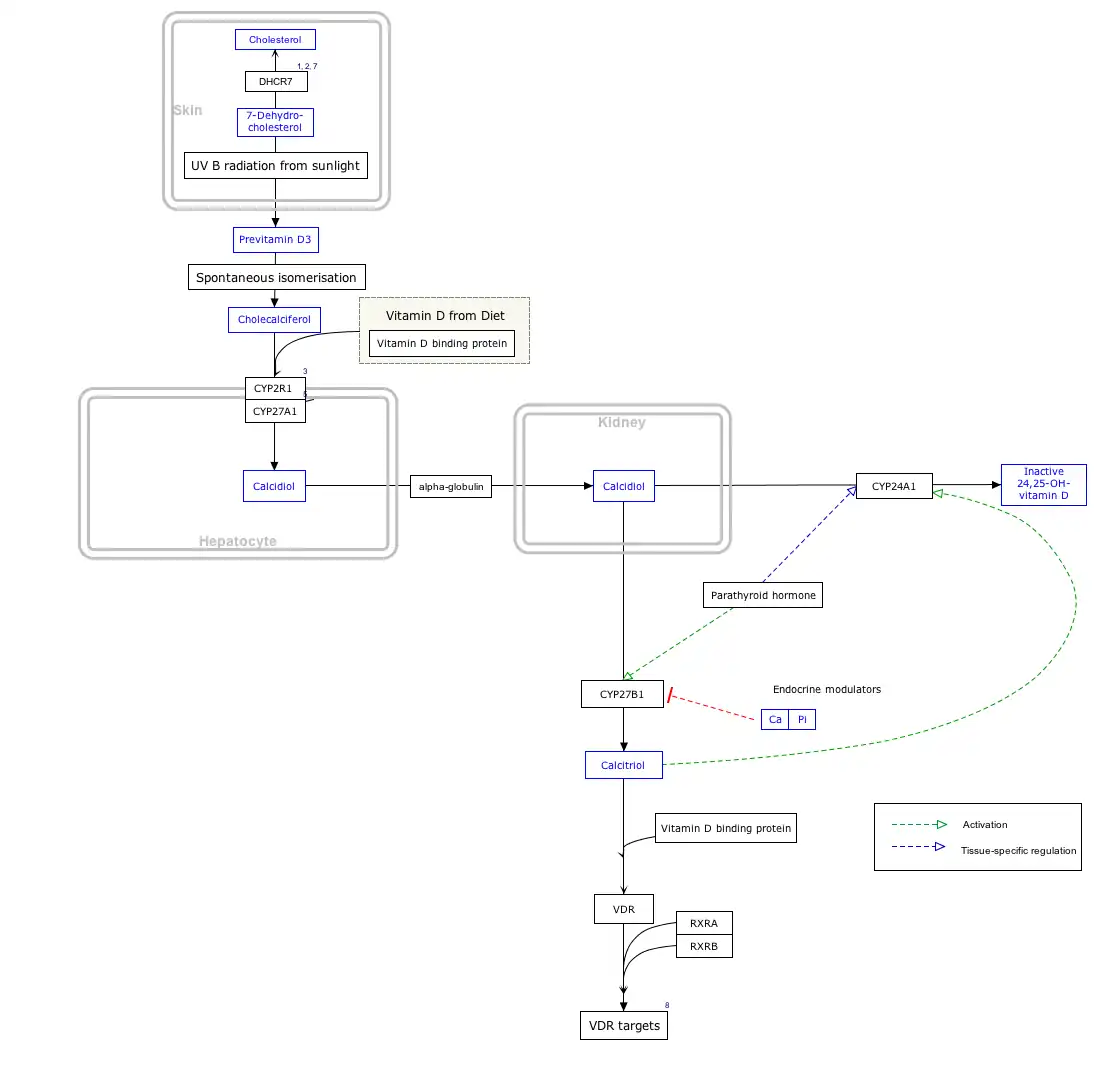

Interactive pathway

Click on View at the bottom to open.

Click on genes, proteins and metabolites below to link to respective articles. [§ 1]

- ^ The interactive pathway map can be edited at WikiPathways: "VitaminDSynthesis_WP1531".

Whether synthesized in the skin or ingested, vitamin D is hydroxylated in the liver at position 25 (upper right of the molecule) to form the prohormone calcifediol, also referred to as 25(OH)D).[3] This reaction is catalyzed by the microsomal enzyme vitamin D 25-hydroxylase, the product of the CYP2R1 human gene.[203] Once made, the product is released into the blood where it is bound to vitamin D-binding protein.[204]

Calcifediol is transported to the proximal tubules of the kidneys, where it is hydroxylated at the 1-α position (lower right of the molecule) to form calcitriol (1,25-dihydroxycholecalciferol, also referred to as 1,25(OH)2D).[1] The conversion of calcifediol to calcitriol is catalyzed by the enzyme 25-hydroxyvitamin D3 1-alpha-hydroxylase, which is the product of the CYP27B1 human gene. The activity of CYP27B1 is increased by parathyroid hormone and also by low plasma calcium or phosphate.[1] Following the final converting step in the kidney, calcitriol is released into the circulation. By binding to vitamin D-binding protein, calcitriol is transported throughout the body.[14] In addition to the kidneys, calcitriol is also synthesized by certain other cells, including monocyte-macrophages in the immune system. When synthesized by monocyte-macrophages, calcitriol acts locally as a cytokine, modulating body defenses against microbial invaders by stimulating the innate immune system.[205]

Deactivation

The bioactivity of calcitriol is terminated by hydroxylation at position 24 by vitamin D3 24-hydroxylase, coded for by gene CYP24A1, forming calcitetrol.[3] Further metabolism yields calcitroic acid, an inactive water-soluble compound that is excreted in bile.[65]

Calcitriol plays a key role in regulating vitamin D levels through a negative feedback mechanism.[206] It strongly upregulates the expression of the enzyme CYP24A1, which inactivates vitamin D. This activation happens through binding of the activated vitamin D receptor (VDR) to two vitamin D response elements (VDREs) in the CYP24A1 gene. VDR also recruits proteins like histone acetyltransferases and RNA polymerase II to enhance this process. At the same time, calcitriol suppresses the production of CYP27B1, another enzyme involved in vitamin D metabolism, by modifying its gene's promoter region through an epigenetic mechanism. Together, these actions help tightly control vitamin D levels in the kidney.[206]

Hormonal

Vitamin D metabolism is regulated not only by the negative feedback mechanism of calcitriol but also by two hormones: parathyroid hormone (PTH) and fibroblast growth factor-23 (FGF-23). These hormones are essential for maintaining the body's calcium and phosphate balance.[206]

Parathyroid hormone (PTH) regulates serum calcium through its effects on bone, kidneys, and the small intestine.Bone remodeling, a constant process throughout life, involves bone mineral content being released by osteoclasts (bone resorption) and deposited by Added internal link to Osteoblast. PTH enhances the release of calcium from the large reservoir contained in the bones. It accomplishes this by binding to osteoblasts, in this way inhibiting the cells responsible for adding mineral content to bones, thus favoring the actions of osteoclasts.[219] In the kidneys, around 250 mmol of calcium ions are filtered into the glomerular filtrate per day, with the great majority reabsorbed and the remainder excreted in the urine.[220] PTH inhibits reabsorption of phosphate (HPO42−) by the kidneys, resulting in a decrease in plasma phosphate concentration. Given that phosphate ions form water-insoluble salts with calcium, a decrease in the phosphate concentration in plasma (for a given total calcium concentration) increases the amount of ionized (free) calcium.[219] A third important effect of PTH on the kidneys is stimulation of the conversion of 25-hydroxy vitamin D into 1,25-dihydroxy vitamin D (calcitriol).[219] This form of vitamin D is the active hormone which promotes calcium uptake from the intestine via the action of calbindin.[221] Calcitriol also reduces calcium loss to urine.[218]

Per the diagram, calcitriol suppresses the parathyroid hormone gene, thus creating a negative feedback loop that combines to tightly maintain plasma calcium in a normal range of 2.1-2.6 mmol/L for total calcium and 1.1-1.3 mmol/L for ionized calcium.[212] However, there are also vitamin D receptors in bone cells, so that with serum vitamin D in great excess, osteoclastic bone resorption is promoted regardless of PTH, resulting in hypercalcemia and its symptomology.[222]